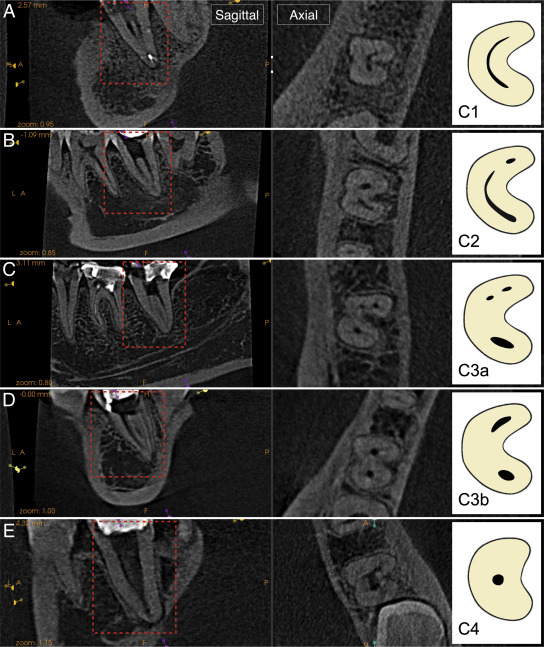

🔴Fan et al in 2004 modified Melton’s method of classification into the following categories 🔴

1️⃣Category I (C1):

The shape is an uninterrupted “C” with no separation or division.

2️⃣ Category II (C2):

The canal shape resembles a semicolon resulting from a discontinuity in the “C” outline, but either angle α or β should be no less than 60°.

3️⃣Category III (C3):

Two or three separate canals and both angles, α and β, are less

than 60°.

4️⃣Category IV (C4):

Only one canal, which is round or oval in cross section

5️⃣Category V (C5):

No canal lumen can be observed (usually seen near the apex only).